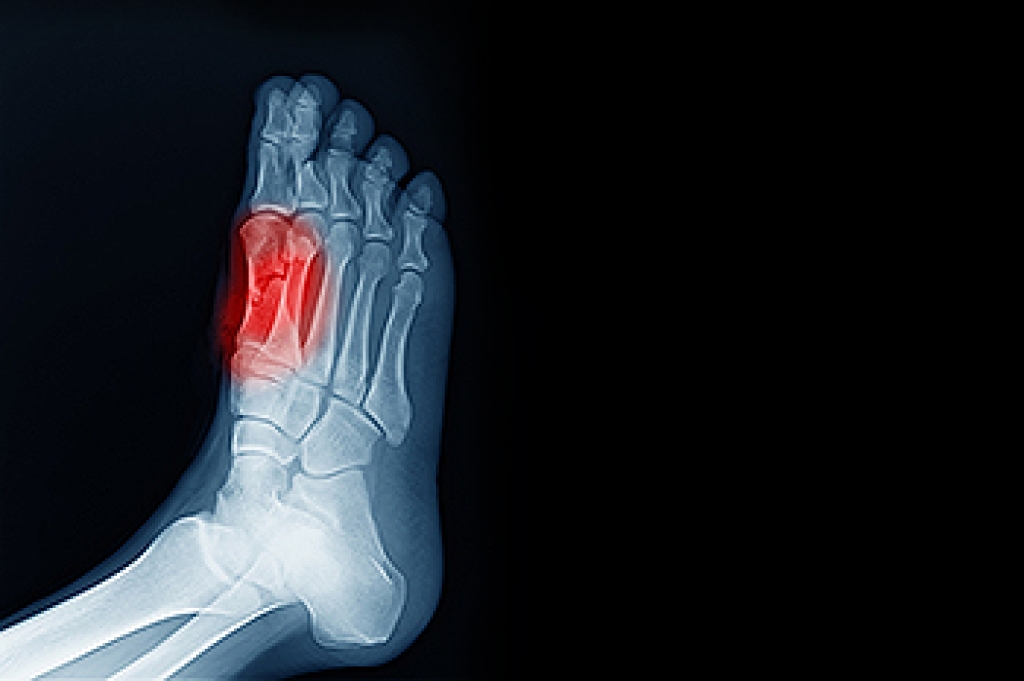

Diagnosis

Due to the wide variety of potential causes of ankle pain, podiatrists will utilize a number of different methods to properly diagnose ankle pain. This can include asking for personal and family medical histories and of any recent injuries. Further diagnosis may include sensation tests, a physical examination, and potentially x-rays or other imaging tests.